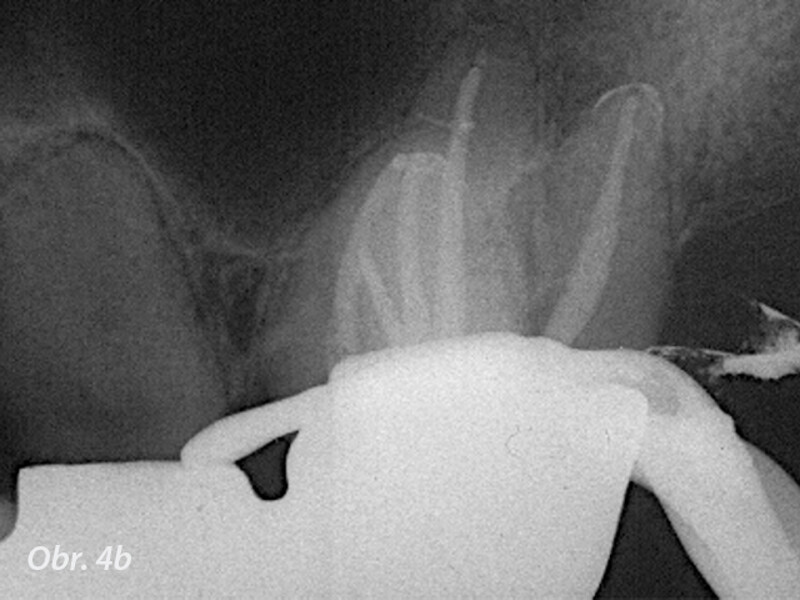

Dentální operační mikroskop v endodoncii